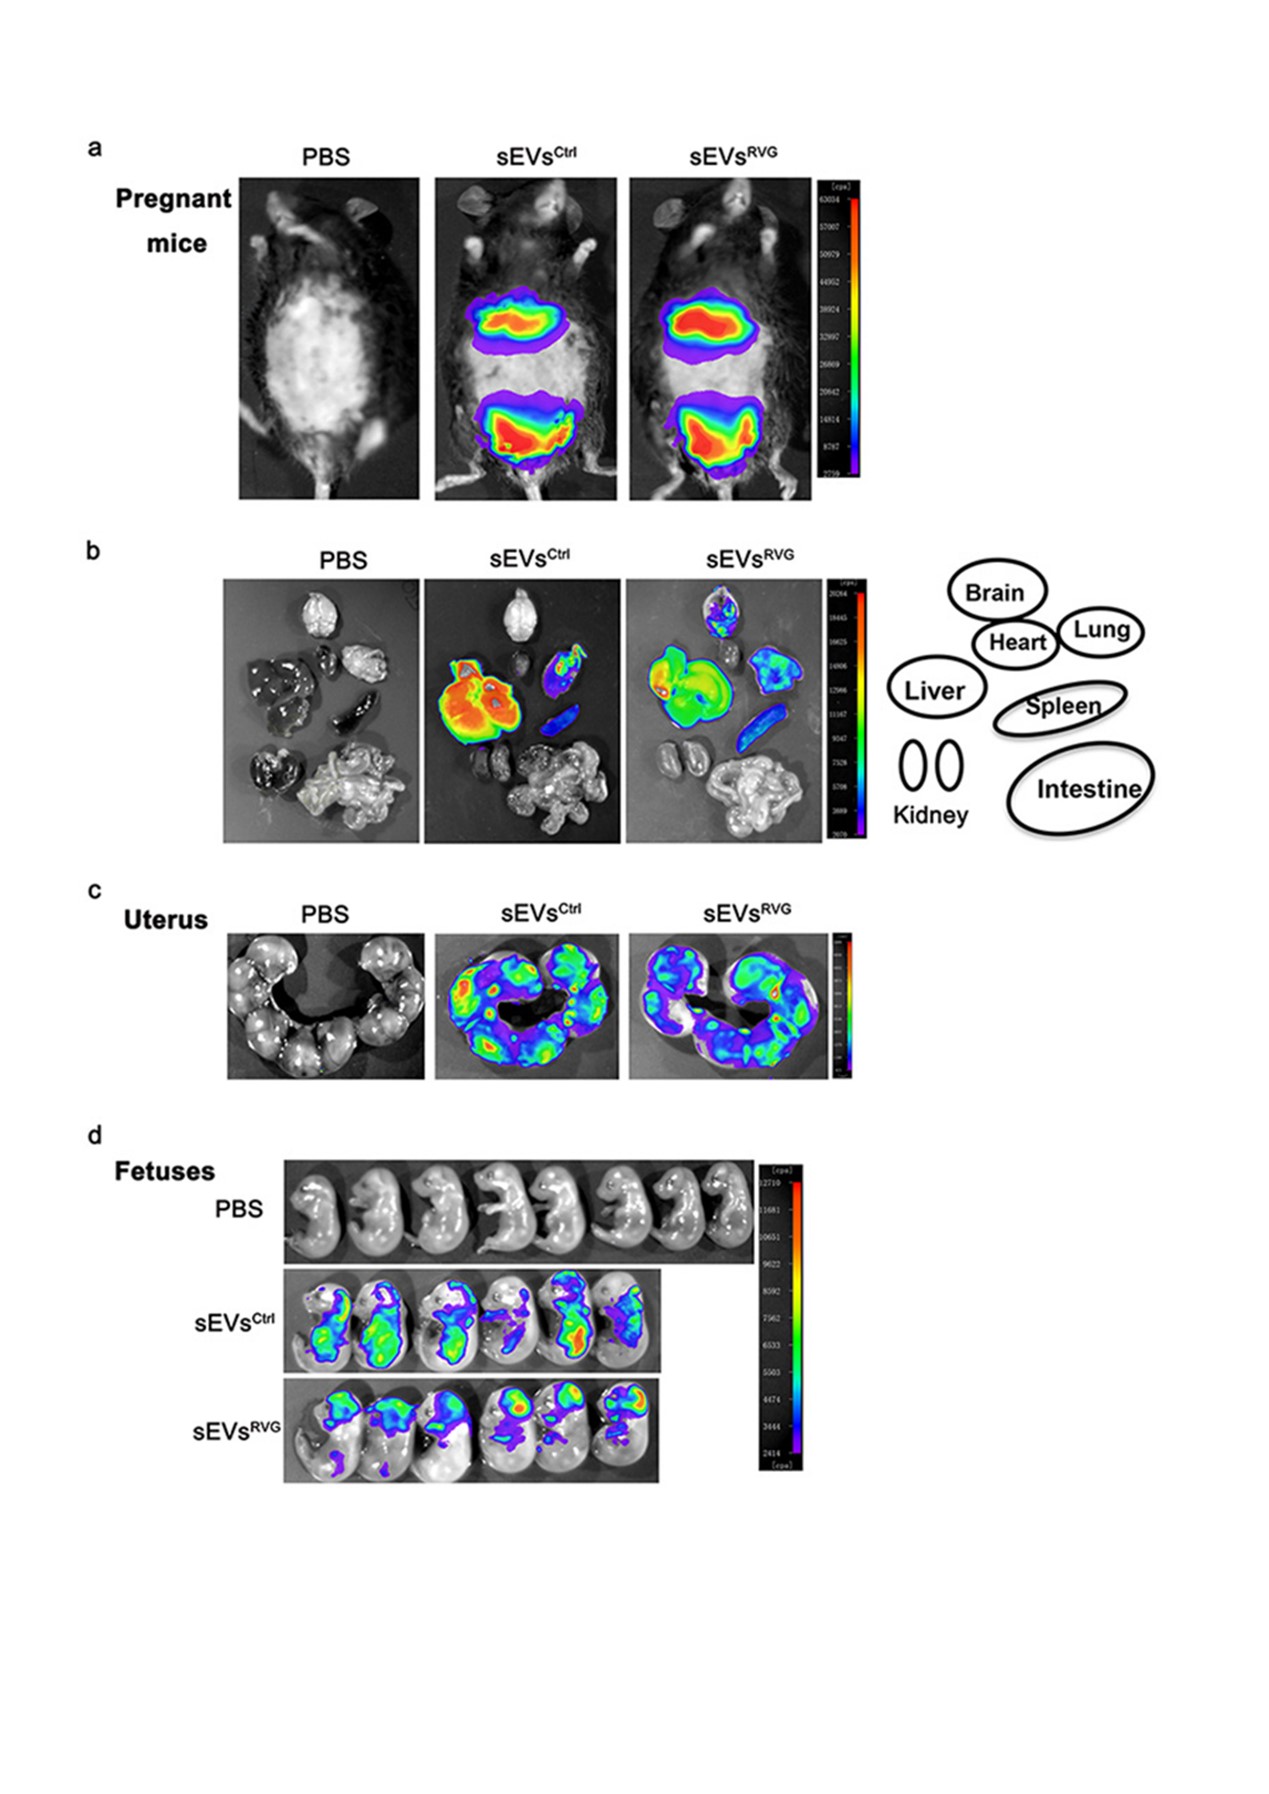

图4:孕鼠模型证明sEVsRVG可跨越胎盘屏障到达靶向组织

通过尾静脉给孕鼠注射sEVsRVG发现其能够穿透胎盘屏障及血脑屏障到达胎鼠脑部神经细胞,验证了sEVsRVG良好的组织穿透力及神经靶向性。